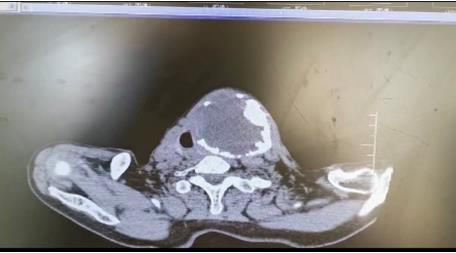

患者朱女士,68歲,頸部包塊呈進(jìn)行性增大50年,來(lái)院后彩超及CT提示左側(cè)甲狀腺腫瘤已經(jīng)超過(guò)10公分并邊緣鈣化,氣管移位較明顯,腫瘤較大屬于罕見,不僅給患者造成心理陰影,還影響了正常生活,偶有憋悶不適,進(jìn)食較大食物感哽咽不適。流動(dòng)醫(yī)院下鄉(xiāng)義診時(shí),發(fā)現(xiàn)包塊已經(jīng)很大了,影響到頸部的活動(dòng)及飲食。醫(yī)生與患者及家屬溝通講解病情,表示我們?nèi)揍t(yī)院能治療。最后患者及家屬抱著試一試的態(tài)度來(lái)到延安大學(xué)咸陽(yáng)醫(yī)院。